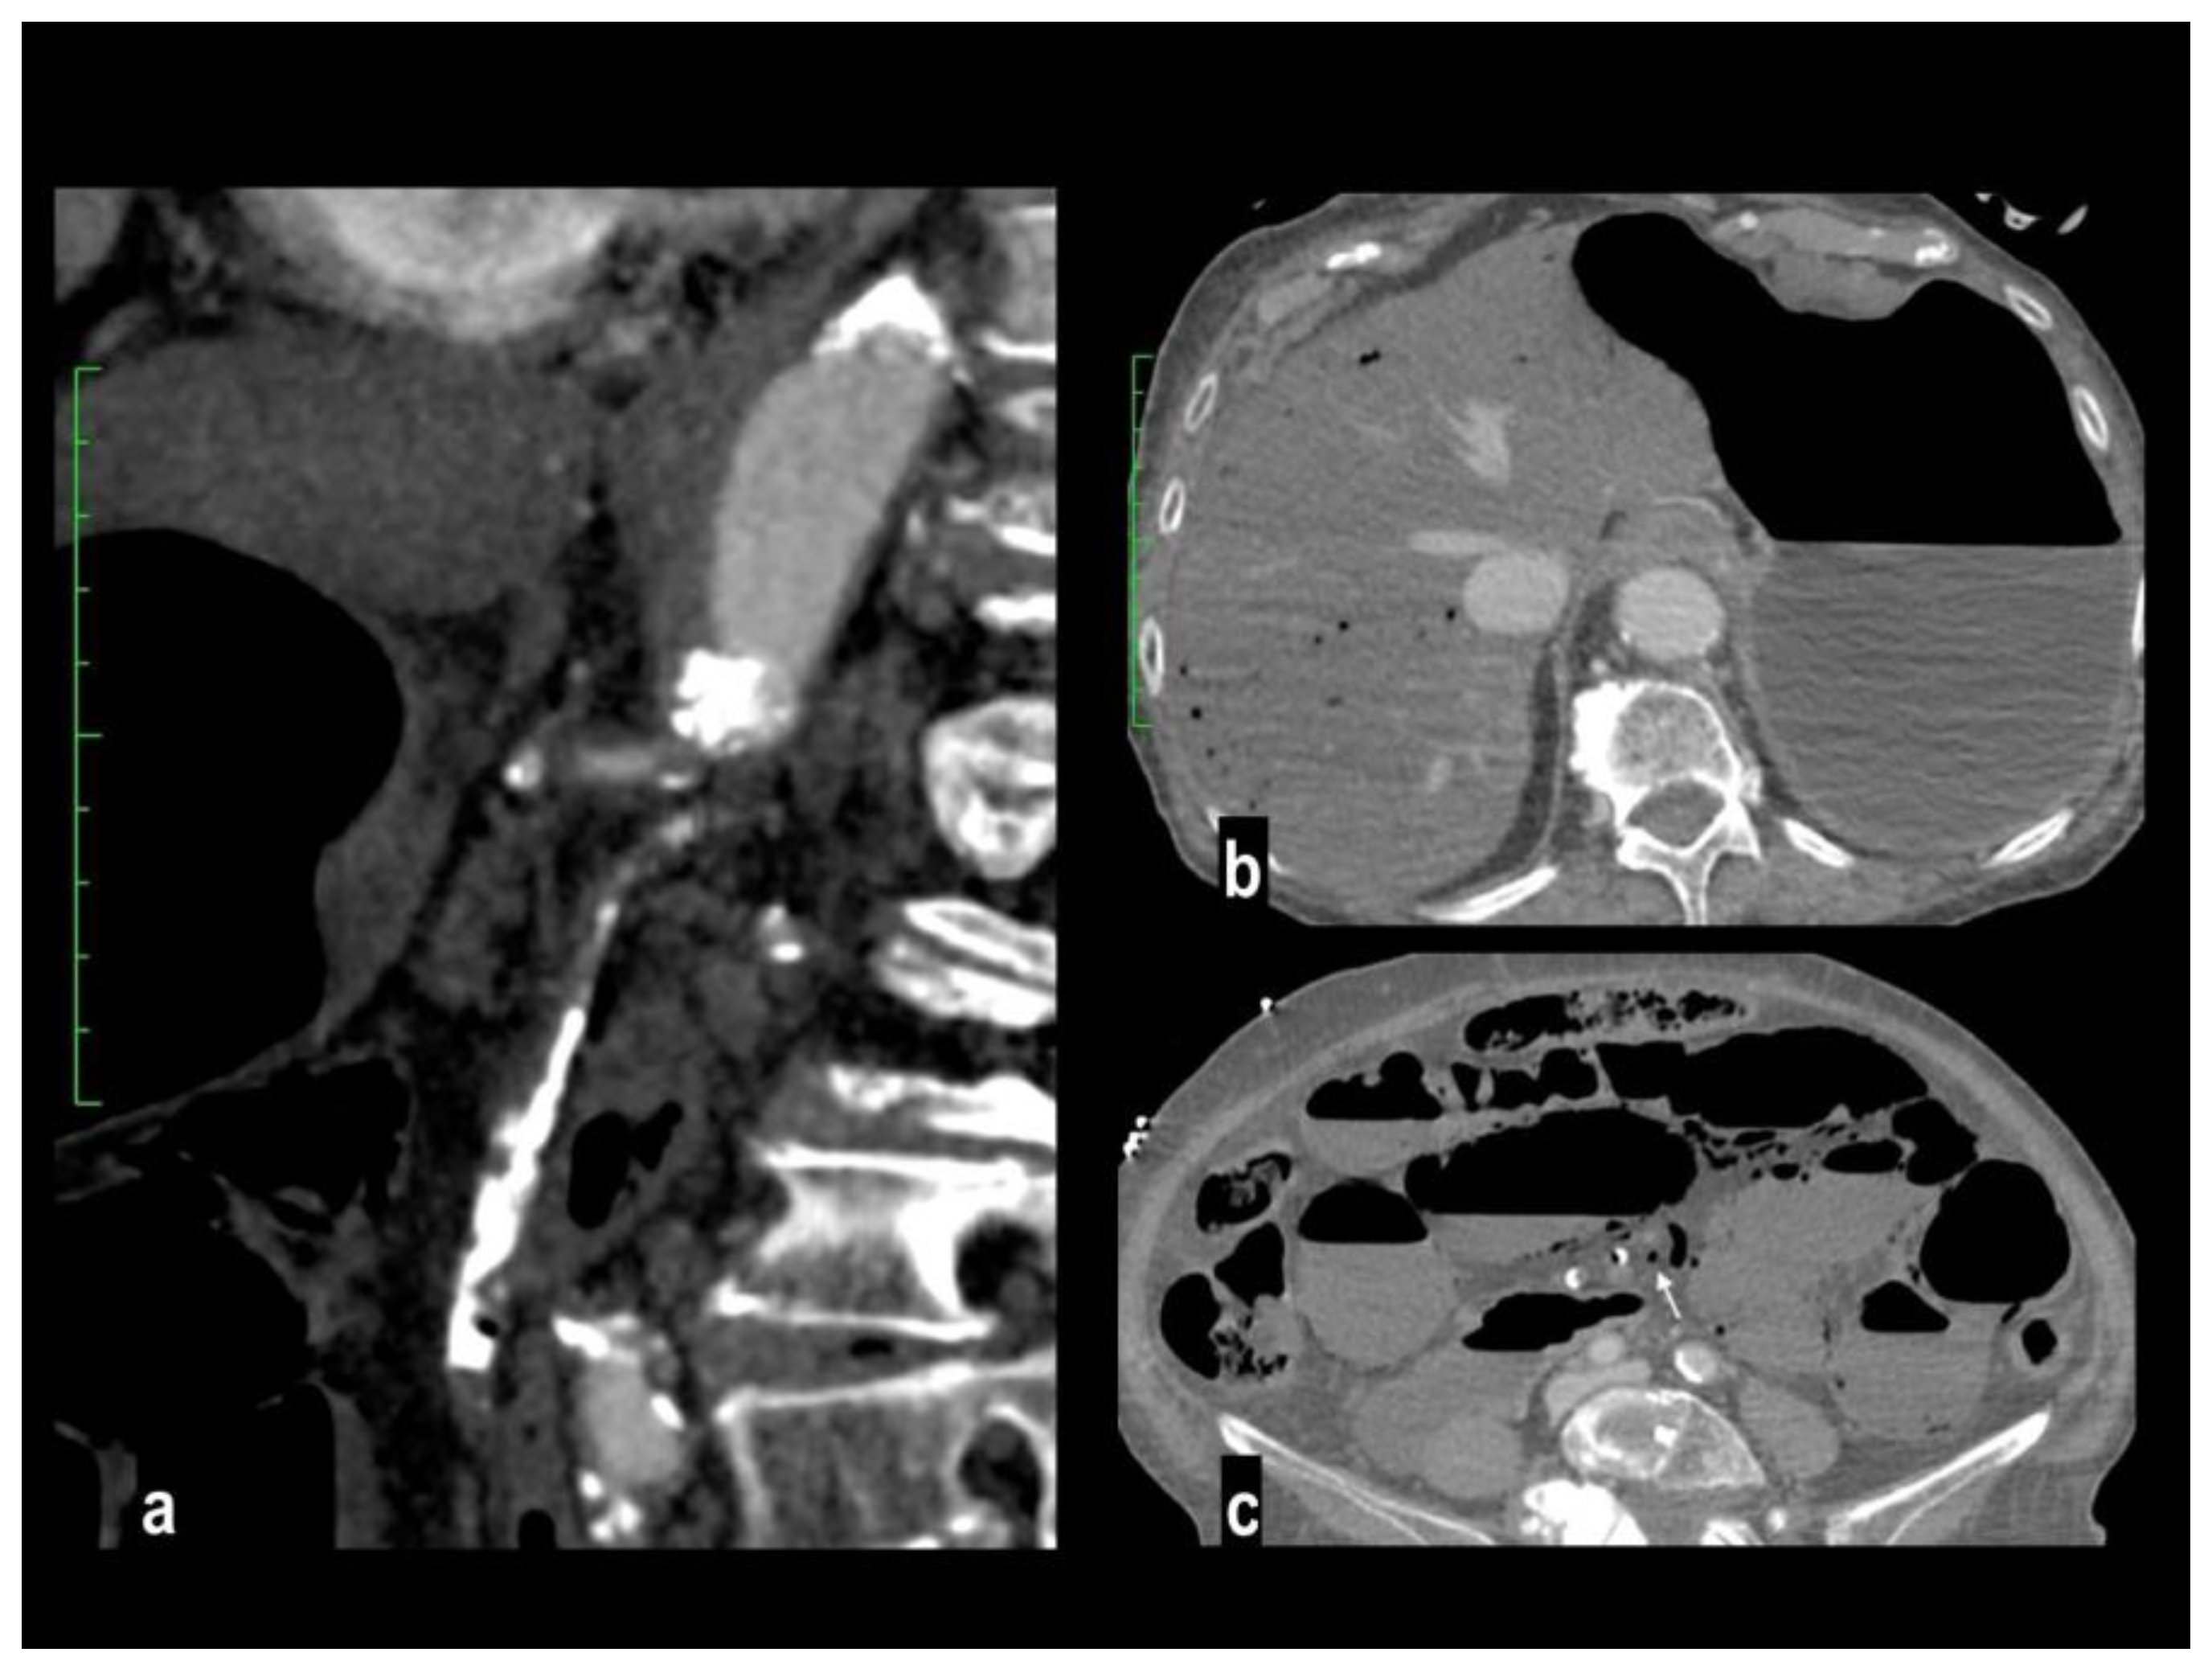

Figure 4. A 78-year-old woman with massive mesenteric ischemia. Atherosclerotic occlusion of the origin of the celiac trunk and the proximal SMA (figure 4a). Intrahepatic pneumatosis and gastrectasia (figure 4b). Hypoenhancing dilated paper-thin bowel wall, parietal pneumatosis and mesenteric venous pneumatosis (arrow) were reported (figure 4c). The patient died a few hours after emergency room access.